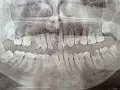

Вчера была у стоматолога. Предположение ― пульпит 8-ки, нужно удаление. Это первый коренной зуб, который предстоит удалить. Большой страх перед этой процедурой. Читала много, боюсь, чтобы не повредили лишнего. Корни 8-ки загнуты. Боюсь, чтоб они не лежали в нервном канале, и при удалении не было проблем.

Хочу сразу успокоить ― корни у нижней восьмерки в канале лежат очень редко, за 25 лет я такого не видел и даже не слышал. А вот корни верхних зубов бывает располагаются в гайморовой пазухе, вот это действительно сложное удаление. Нижние же зубы мудрости сложны в удалении только, если они лежат под костью, полностью заросли, так называемые ретинированные зубы.

Но у Вас, если его смотрел доктор и предположил пульпит, очевидно, что коронковая часть зуба видна. Даже, если корни загнуты, для хирурга-стоматолога ― это ординарная ситуация. Удаление, возможно, будет считаться сложным, но это означает лишь то, что врачу придется приложить чуть больше усилий.